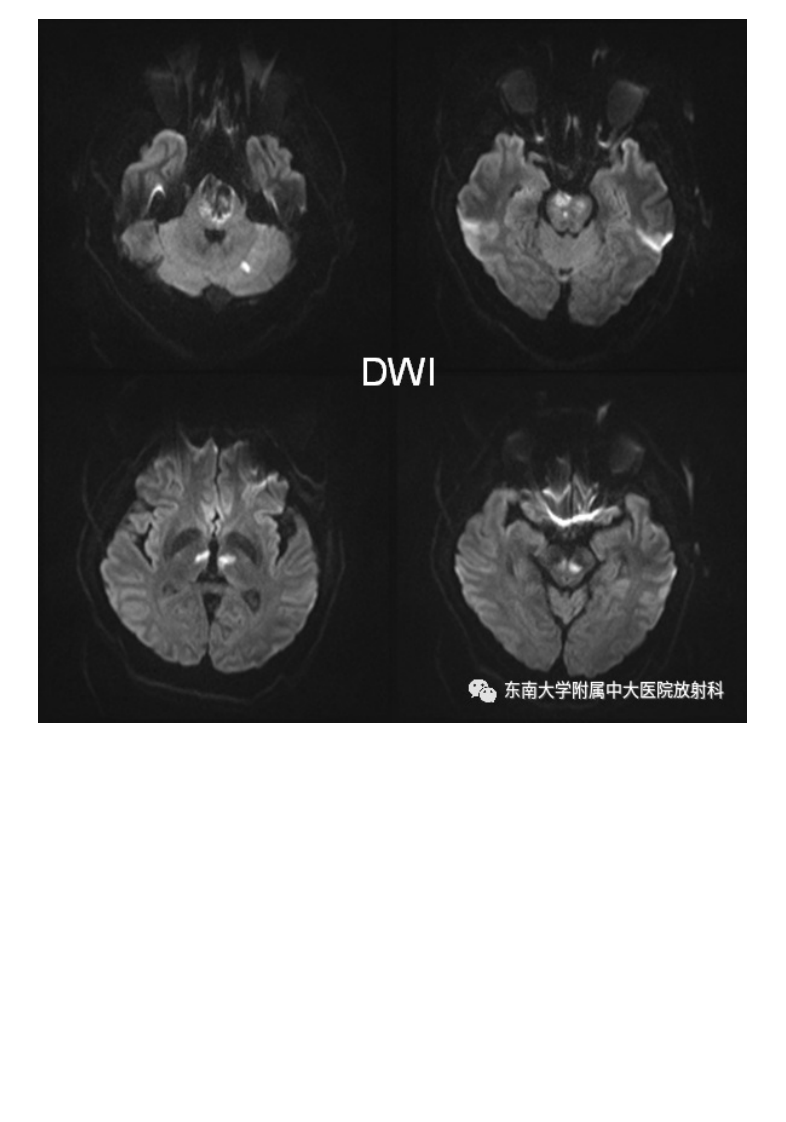

20210509_3【晨读结果公布】2021.05.08神经系统疾病——基底动脉尖综合征.pdf